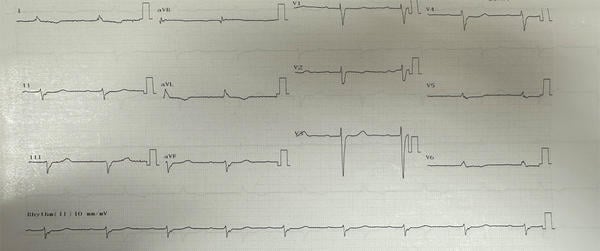

ECG